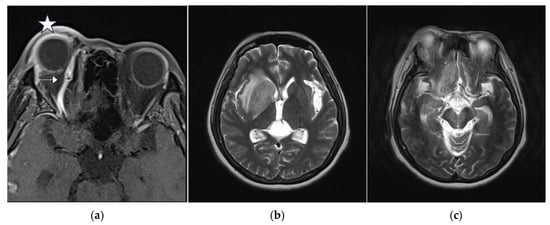

Figure 3.

(a) Brain magnetic resonance imaging (MRI) axial view, T1-weighted imaging with contrast disclosed engorgement of right superior ophthalmic vein (arrow head), and swelling of right orbital cavity (star); (b) brain MRI axial view, T2-weighted imaging show high T2 signal change in right corpus striatum; and (c) axial view of brain MRI T2-weighted imaging show enhancement at right insular lobe, right frontal inferior lobe, right medial temporal lobe, midbrain, and pons, which indicate perifocal cerebral edema.

Brain MRI was followed up 3 days after endovascular treatment, which disclosed significantly decreased engorgement of the right SOV (Figure 5a) and less perifocal edema in the right corpus striatum, midbrain, and pons (Figure 5b,c). Consequently, a conservative strategy was implemented to address residual CCF. We conducted a follow-up DSA one month after the TVE. The DSA revealed that the residual CCF had spontaneously resolved without additional cortical reflux (Figure 6a,b). The patient experienced a complete remission of ophthalmic symptoms (Figure 2c); her conscious level and the intraocular pressure of her right eye (Table 1) both had a favorable recovery.

Figure 5.

(a) Brain MRI was followed up 3 days after endovascular treatment: axial view of brain MRI T1-weighted imaging with contrast disclosed significantly decreased engorgement of the right superior ophthalmic vein (arrow head); (b,c) brain MRI axial view, T2-weighted imaging showed less perifocal edema in the right corpus striatum, midbrain, and pons comparing to the condition before endovascular treatment.